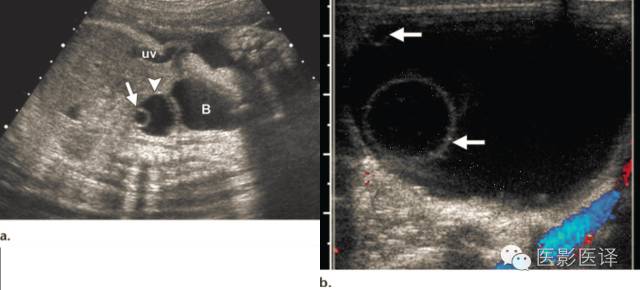

Nussbaum等最早将新生儿卵巢囊肿分为单纯性和复杂性。单纯性卵巢囊肿是圆的、无回声的、单房和薄壁的(图1)。它们更经常为单侧而非双侧、更经常为腹内而非盆腔内。单纯性囊肿内偶尔可见单个分隔(图2)。直径小于20mm的卵巢囊性结构被认为是成熟卵泡,为生理性而非病理性。直径大于20mm的囊肿则考虑为异常。“子囊”征描述的是囊内一个小的、圆形、无回声结构(图3)。既往报道认为这是卵巢囊肿的特征。【在一个23例囊性病变的研究中(包括新生儿、婴儿及儿童),11例发现子囊,占卵巢囊肿的82%(敏感度82%,特异度100%,阳性预测值100%),在其他囊性病变中未发现子囊,包括淋巴管瘤、肠重复畸形、肠囊肿、胎粪假性囊肿、阴道积液和脐尿管囊肿。】

图3:单纯性卵巢囊肿。(a)矢状位胎儿超声图像显示一个边界清楚薄壁腹内囊肿(箭头),其内可见一个子囊(箭)。囊肿位于膀胱(B)上方腹中线区。Uv=脐静脉。(b)同一病人轴位超声多普勒图像显示在薄壁卵巢囊肿中有两个子囊(箭头)